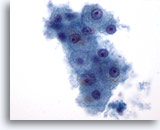

画像 2: 肝FNA – 良性肝細胞

反応性変化を来した良性肝細胞の集塊。細胞境界が明瞭な立方形の細胞が認められます。不透明な細胞質には空胞が認められるものもあれば、幾分顆粒状を呈するものもみられます。辺縁部は擦り切れた状態を呈しています。核はわずかに大小不同で、二核を有する細胞も認められます。小型の核小体がみられます。

40倍

画像 2

肝FNA – 良性肝細胞

反応性変化を来した良性肝細胞の集塊。細胞境界が明瞭な立方形の細胞が認められます。不透明な細胞質には空胞が認められるものもあれば、幾分顆粒状を呈するものもみられます。辺縁部は擦り切れた状態を呈しています。核はわずかに大小不同で、二核を有する細胞も認められます。小型の核小体がみられます。

40倍